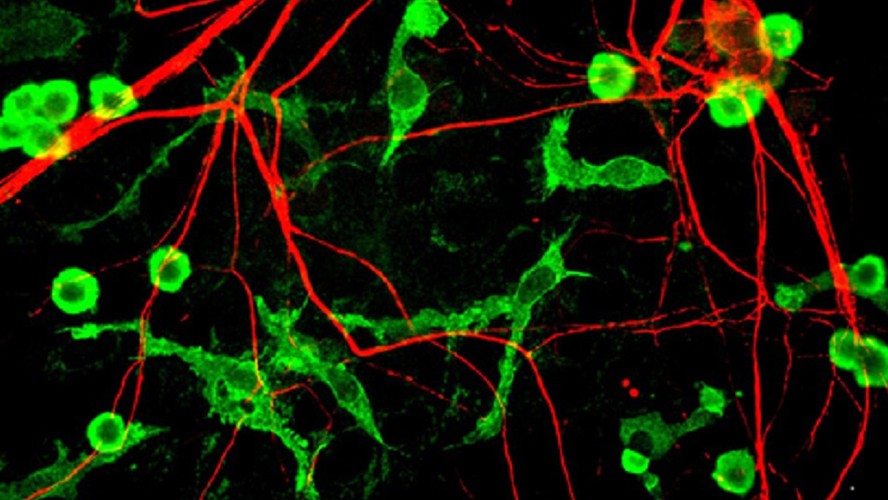

Un equipo de científicos de la Escuela de Medicina de la Universidad de Yale (Estados Unidos) logró grabar un video que muestra cómo el cerebro de un ratón destruye las neuronas muertas.

En él se puede ver cómo una neurona muerta (en color rojo) es dirigida y rodeada por células inmunes del cerebro, llama microglia. Ésta fragmenta la neurona muerta y consume su contenido, evitando que bloquee la actividad de las neuronas circundantes.

"La apoptosis (muerte programada de células) es un proceso fundamental de vida. Remover una célula muerta de forma eficiente es crucial para el desarrollo y el mantenimiento de la salud. Por primera vez, investigadores de la Universidad de Yale capturaron imágenes que muestran cómo el cerebro dispone de las neuronas muertas. Células específicas llamadas microglia acuden y envuelven el cuerpo de una neurona muerta mientras otras células del cerebro, llamadas astrocitos, ayudan a limpiar las ramas de conexión de la neurona. Según el autor, entender este proceso puede ayudar a los científicos a tratar trastornos del desarrollo neurológico, lesiones cerebrales y enfermedades neurodegenerativas asociadas con el envejecimiento".